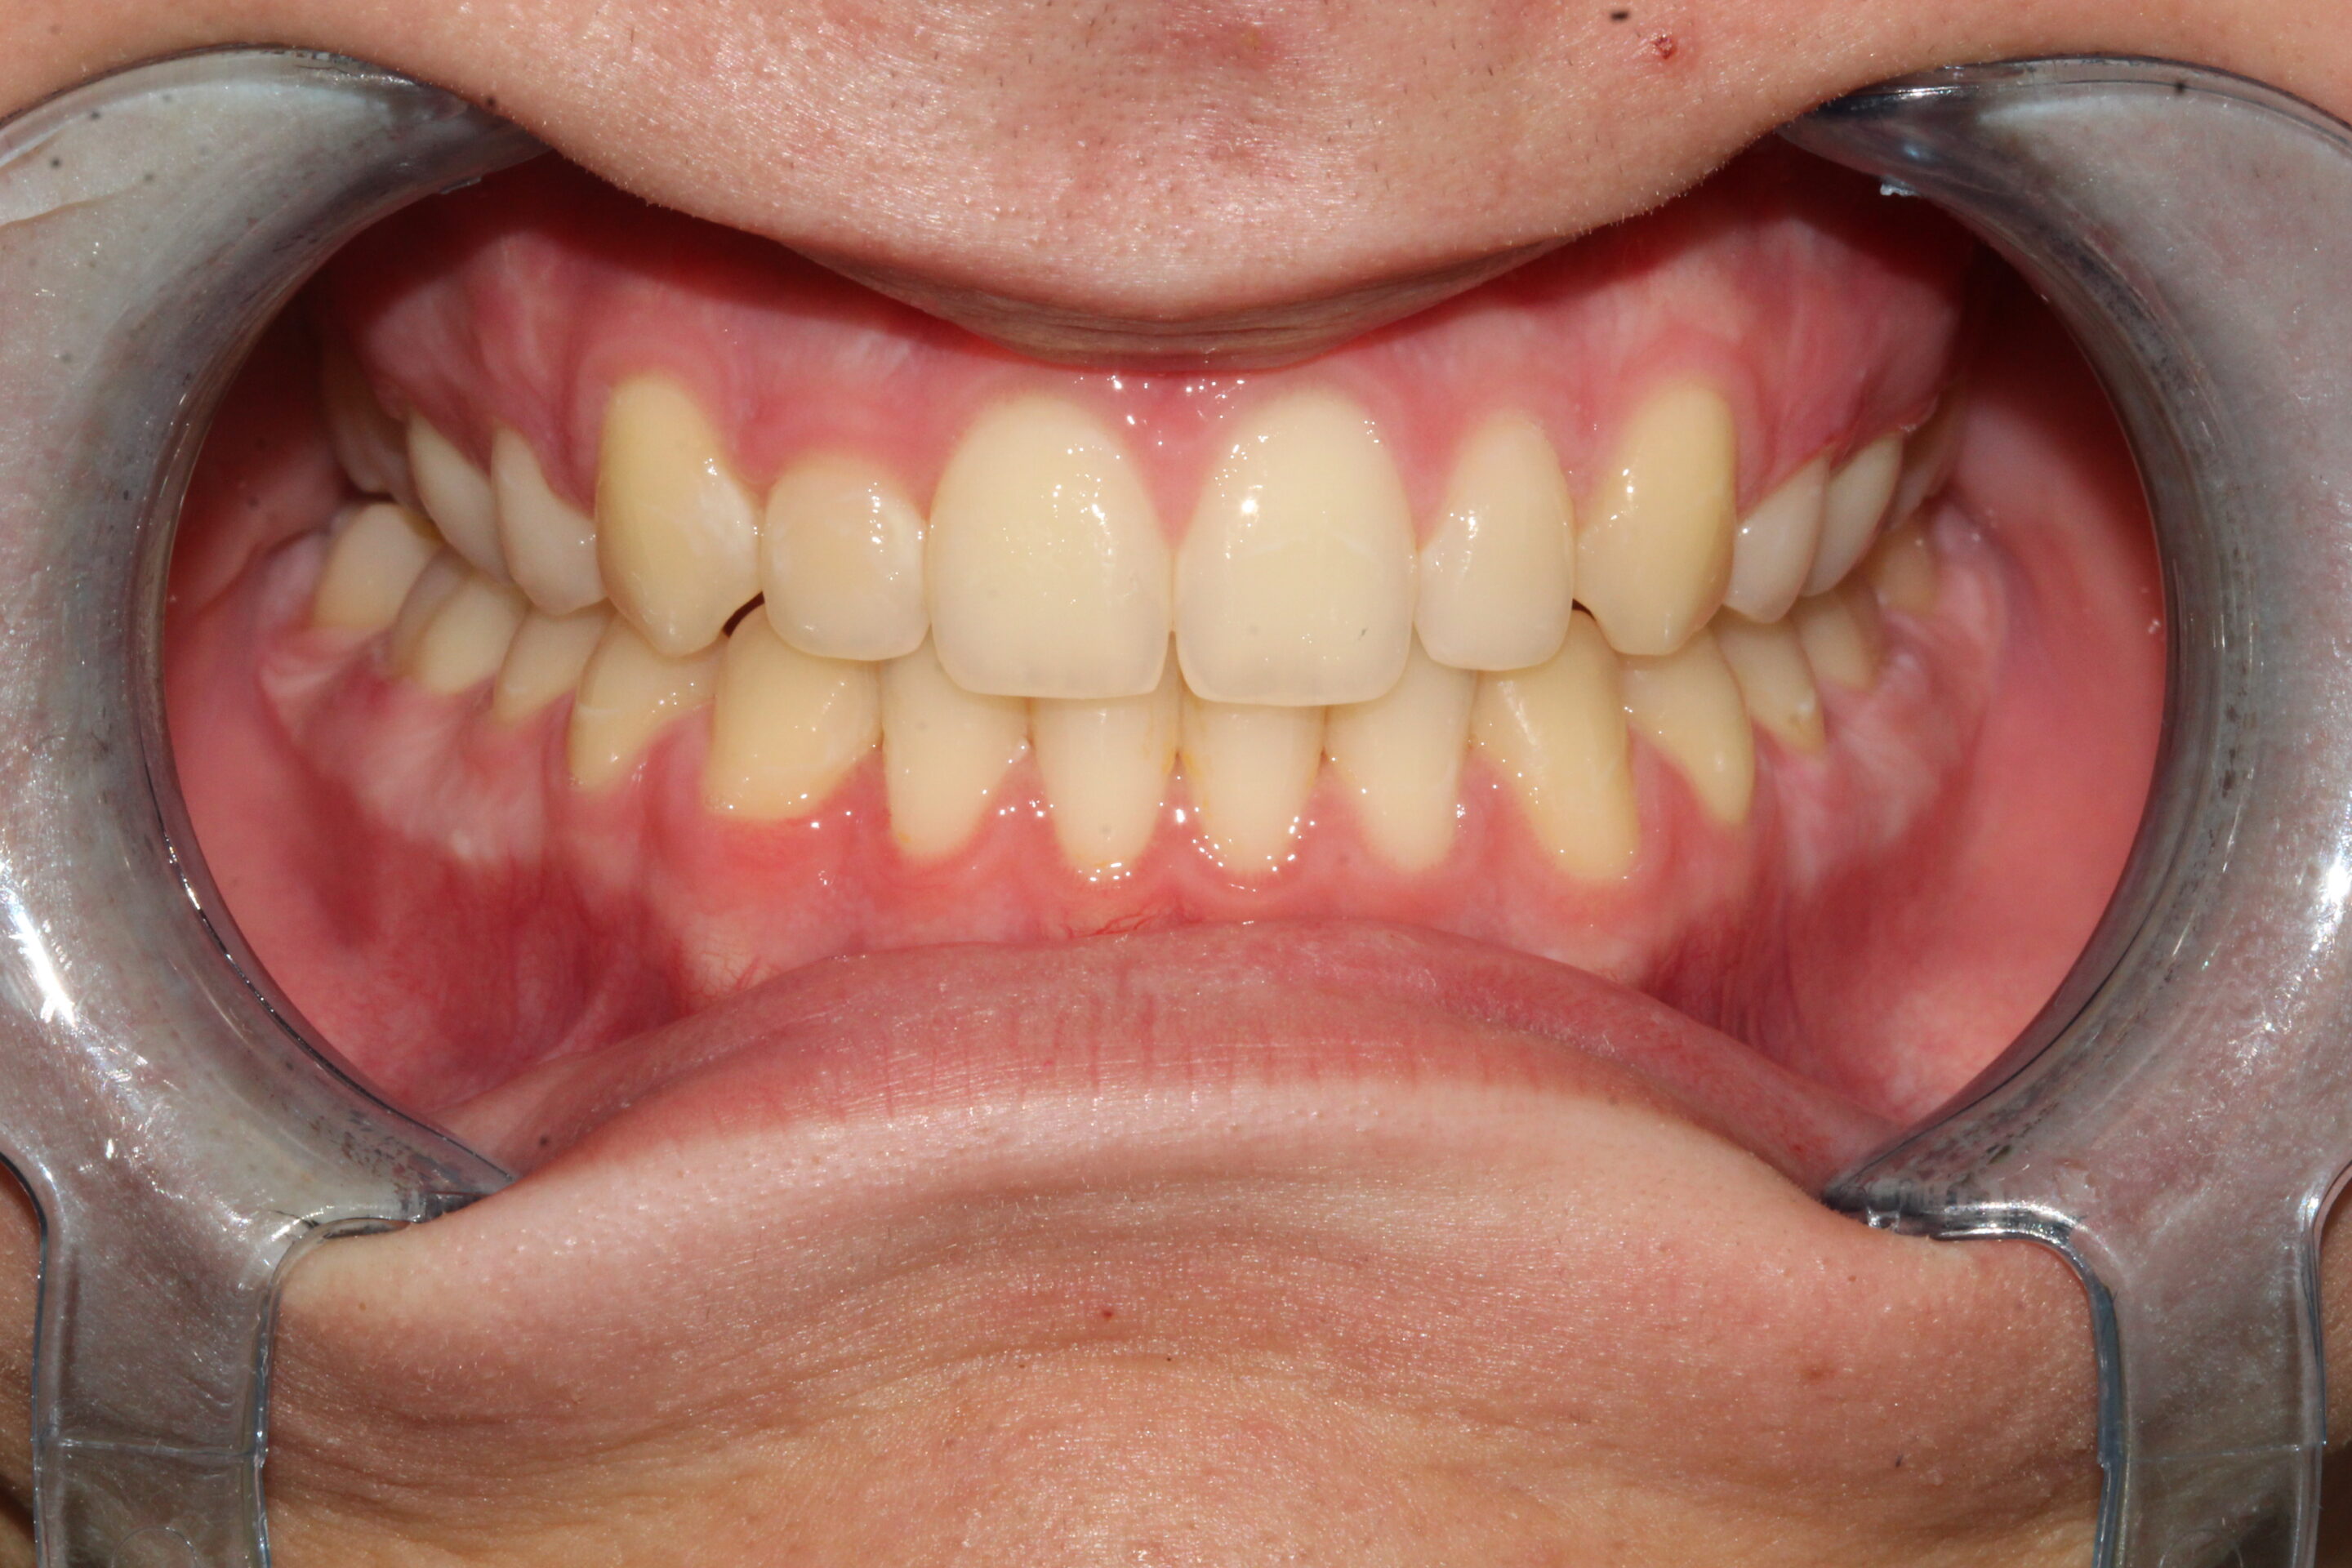

Fogív rendezés

A frontfogak torlódását és a harapás eltérését sikeresen korrigáltuk, így a fogív szabályossá vált, a rágófunkció javult és az esztétikai megjelenés is sokkal harmonikusabb lett.